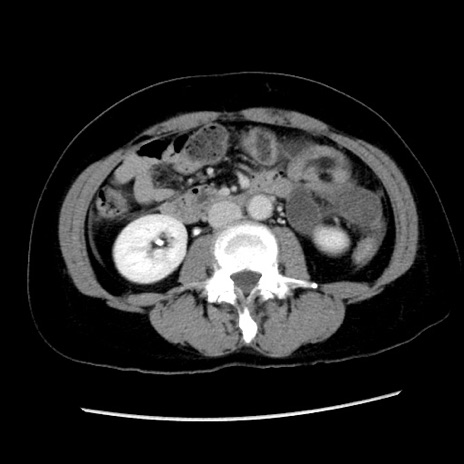

症例10(横断像)

【症例】 50歳代女性

【主訴】 腹痛

【現病歴】前日生レバーを食べた。今朝に排便あり。 昼前に突然発症の腹痛を生じ、当院救急外来を受診した。

【既往歴】 子宮筋腫にてで子宮全摘後

【身体所見】 意識清明、腹部:平坦、軟、下腹部やや左を中心に圧痛・反跳痛あり、筋性防御あり

【データ】WBC 7800、CRP 0.07